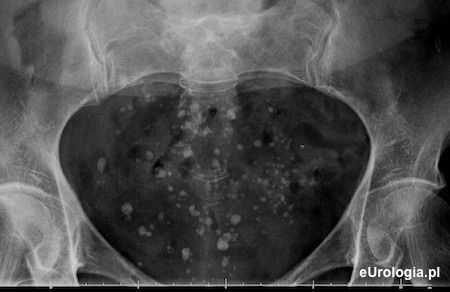

Flebolity w miednicy małej - zdjęcie rentgenowskie

Liczne flebolity miednicy małej widoczne na zdjęciu przeglądowym jamy brzusznej w pozycji leżącej.

Flebolity są zwapnieniami w splotach żylnych miednicy małej. Nazwa flebolit pochodzi od greckich słów: phlebos - żyła lub naczynie żylne oraz lithos - kamień. Flebolity nie wymagają leczenia i nie są objawem chorobowym. Flebolity widoczne na zdjęciach rentgenowskich są wysyconymi solami mineralnymi skrzeplinami w naczyniach żylnych miednicy małej.